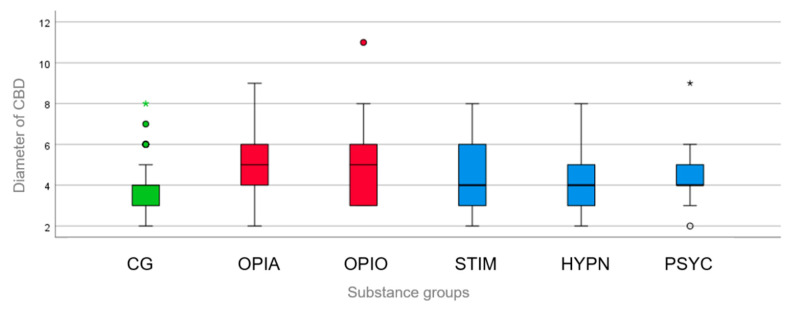

For both subgroups of “opiates” and “opioids”, there was a strong statistically significant difference between the CBD diameter (being wider) in those groups compared to that in the control group (both p = 0.001) (Figure 4). Diameters > 8 mm were found in both subgroups, whereas only one CBD with a diameter of >8 mm was found in the psychotropic drugs subgroup, and none in the control group. For the other three subgroups, there was no statistically significant difference between the CBD diameter in the intoxication subgroups compared with that in the control group (stimulants, p = 0.462, r = 0.039; hypnotics, p = 0.244, r = 0.161; psychotropic drugs, p = 0.142, r = 0.299) (Figure 4).